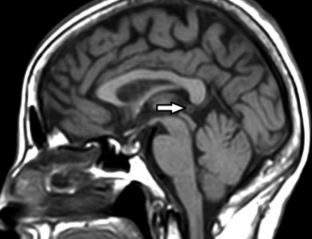

RM de cerebro, corte sagital ponderado en T1. La anatomía normal de la glándula pineal se encuentra modificada por la presencia de una imagen de apariencia quística simple (flecha).